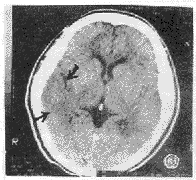

图3 左偏瘫13h,右颞皮质楔形密度减低与白质一致(皮质征),局部脑沟消失,侧裂池、侧脑室三角区变小(占位征)。

幕上209例,大脑中动脉供血区197例,大脑前动脉供血区8例,大脑后动脉供血区4例,右小脑半球1例。CT征象阴性40例,致密动脉征表现为平扫CT图像上脑动脉密度增高,超过脑皮质密度,低于钙化密度。豆状核征表现为豆状核轮廓模糊,密度与脑白质一致或稍低(图1)。脑岛带征表现为脑岛带区灰白质界面模糊,灰白质密度一致(图2)。低密度灶分腔隙性(<1cm为小腔梗,1~1.5cm大腔梗)和片状(>1.5cm)。占位征表现为邻近脑室、脑池、脑沟变小(图3)。皮质征表现为皮质局限性密度减低,与脑白质密度一致(图4)。各征象在不同时间出现率见表1,敏感性等指标测定结果见表2。